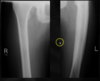

What is seen here in regards to density? (left is abnormal)

Permeative/Motheaten